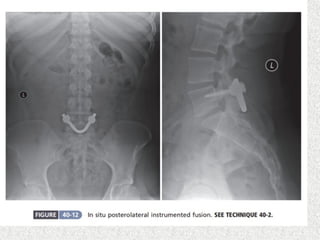

 Instrumented posterolateral fusion(wiltse &

spencer)

 Instrumented posterolateralfusion(wiltse & spencer)  No significant neurological symptom  Good spinal alignment  Sufficient surface area >2cm2 of transverse process  Less surface area for posterolateral fusion  Posterior only approach with circumferential fusion(posteior/transforaminal lumbar interbody fusion PLIF/TLIF)  Ant lumbar interbody fusion with post supplemental fixation  Used if small transverse process  Salvage procedure if non union in posterolateral fusion  Patients with neurological symptom  Direct/indirect decompression also needed